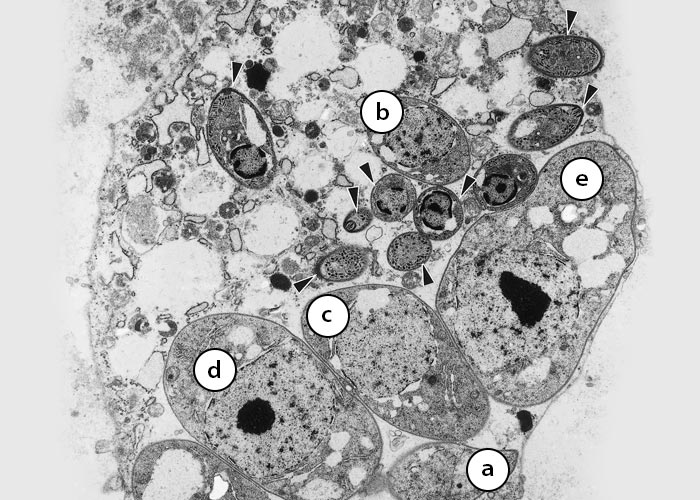

Sarcocystis neurona schizonts are found in neurons, various glial cells and resident macrophages in the brain and spinal cord.40, 48, 76, 142 They divide by endopolygeny:142 the nucleus of the parasite becomes multilobed and eventually each nuclear lobe is incorporated into two budding merozoites (Figure 3 and Figure 4). Schizonts in tissue sections are approximately 5 -35 × 5 -20 μm in size and contain up to 40 merozoites, sometimes arranged in a rosette around a residual body.55 (Figure 4) Merozoites are approximately 5 × 1 μm in size. Ultrastructurally, S. neurona schizonts are located in the host cell cytoplasm without a parasitophorous vacuole (Figure 4). Merozoites contain a conoid, micronemes, a nucleus, a prominent lipid body posterior to the nucleus, but no rhoptries.55, 142 Schizonts have been identified in extraneural tissues of some hosts including the muscles of a dog,36 turbinates of a ferret11 and retina of a dog36 and a sea otter.66 (Figure 4)

Figure 3 Transmission electron micrograph of a schizont of Sarcocystis neurona in a bovine monocyte showing merozoites budding from residual body (Rb). Some of the merozoites are still attached (arrowheads) to the residual body; conoid (Co); dense granule (Dg); host cell nucleus (Hcn); mitochondrion (Mi); microneme (Mn); micropore (Mp); nucleus of merozoite (N)